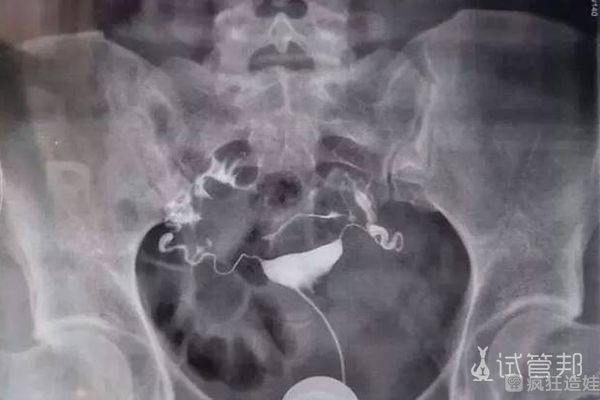

老婆双侧输卵管堵塞医生直接让做试管婴儿可行吗?

老婆双侧输卵管堵塞医生直接让做试管婴儿可行吗?双侧输卵管伞完全阻塞会直接影响受孕,可以手术疏通。但是复发的概率大,感染的风险高。针对这种情况,医生普遍主张患者直..

双侧输卵管积水做二代试管婴儿一次成功经历分享,这4大真实经验请收下

根据相关的资料是可以得到,女性出现输卵管积水的几率是在10-30%左右的样子,而因为输卵管积水大多数都是因为输卵管炎症等引起的,有的女性是单侧的,有的是双侧的。而且,..

双侧输卵管堵塞备孕有方法,二代试管婴儿or疏通并非你说了算

自然受孕过程中精子与卵子在输卵管相遇并结合,从而在内膜上扎根发育,而双侧输卵管堵塞就造成了精子与卵子无法相遇从而导致女性不孕,面对这一病症的治疗上很多人纠结于是..